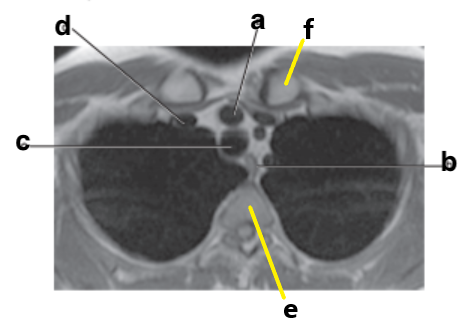

What is letter a ?

Left Ventricle

What is letter e ?

Vertebral body

What is letter c ?

Hemiazygos vein

Which letter is the descending thoracic aorta ?

e

What is letter g ?

Descending aorta

Trachea

Thoracic vertebra